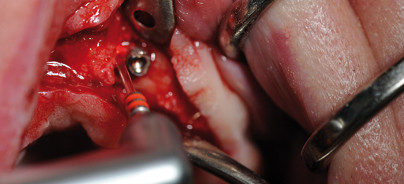

Nach umfassender Aufklärung und Beratung des Patienten wurde die Implantatentfernung mittels Lasertechnik zeitlich geplant. In interdisziplinärer Zusammenarbeit mit dem Hausarzt und Internisten des Patienten wurde eine temporäre Umstellung von Marcumar auf ein Low-Dose-Heparin (Clexane) veranlasst und der Quickwert des Patienten zum Operationstag auf 48% angehoben. Die nun nachfolgend beschriebene Implantatentfernung erfolgte einschließlich der Schnittführung mit dem KaVo Key 3 Plus-Laser. In den Abbildungen 4a bis c sind das Arbeitsende des KaVo Handstückes 2062 mit einer kurzen rigiden Faser sowie die verwendeten Einstellungen des sehr übersichtlichen Displays illustriert. Nach der Mukoperiostlappenbildung ließ sich Regio 23 der tieffrakturierte distale Anteil des Titanimplantates darstellen (Abb. 5). Für die initiale Osteotomie und Freilegung des Implantates (Abb. 6) wurde zunächst das sogenannte Fensterhandstück 2060 (Abb. 7) genutzt, wobei hiermit auch möglicherweise bakteriell besiedeltes Gewebe sicher und schonend abgetragen werden konnte und ein Versprengen in das umgebende Knochengewebe weitestgehend vermieden werden sollte.10,11 So wurden mit dem Fensterhandstück 2060 im Short-Pulse-Modus ca. 30% der Implantatlänge freigelegt (Abb. 8). Die Laserparameter waren bezüglich Energie 250mJ, Frequenz 20Hz und einer Spitzenleistung von 5,0 Watt im Short-Pulse-Modus eingestellt, wie die Abbildung 8a zeigt. Für den Energie- und Laserlichteintrag in den Knochenbereich kam danach das Winkelhandstück 2261 mit dem roten Saphirmeisel (Abb. 9) zur Anwendung. Das intraoperative Foto in Abbildung 10 zeigt, dass unter ständiger Bewegung und Spraywasserkühlung das zu entfernende Implantatfragment mit dem roten Saphirmeisel in geringem Abstand, aber sozusagen auf „Tuchfühlung“, umkreist wurde. Eine Kontrolle der Effektivität kann ein erfahrener Behandler mehr fotoakustisch als visuell durchführen. Die Abbildungen 11 und 12 bezeu-gen das schrittweise Freilegen des Implantates durch Fort- und Einleitung des Laserlichtes in die tiefer gelegenen Knochenbereiche.

Aufgrund seiner hohen Absorptionsrate im Wasser hat sich der Er:YAG-Laser mit einer Wellenlänge von 2.940nm als effektives Werkzeug zur Bearbeitung von oralen Geweben, also auch Knochen, etabliert.7 Mit dem richtigen Arbeitsabstand der Saphirspitze zum Knochengewebe und einer effektiven Spülung kann klinisch außerordentlich schonend gearbeitet werden. In diesem dokumentierten Patientenfall überzeugte der präzise Abtrag von Knochen in direkter Nähe zum Implantat, aber auch von gefährdeten anatomischen Nachbarstrukturen wie der Nasennebenhöhle, ohne dass die Titanoberfläche des zu entfernenden Implantates beschädigt oder zerstört wurde. Somit wurden keine Titanpartikel in das benachbarte Knochengewebe versprengt, wie es oft durch den Einsatz rotierender Explantationsfräsen oder durch Nutzung anderer chirurgischer Instrumente von Kollegen berichtet wurde. In Abbildung 14 ist das freigelegte Implantatfragment zu sehen. Diese Nahaufnahme zeigt, dass der ohnehin schmale Processus alveolaris in Regio 22 bis 24 weitestgehend geschont und erhalten werden konnte. Um ein unkontrolliertes Lösen und womöglich eine Aspiration des Fremdkörpers zu ver-meiden, wurde dieser sicher mit einer tiefgreifenden Extraktionszange gefasst und der Kavität entnommen (Abb. 14 und 15). Um trotz des sehr kleinen Knochendefektes eine rasche Regeneration und knöcherne Durchbauung des Processus alveolaris zu begünstigen, wurde zusätzlich ein Augmentationsmaterial in den knöchernen Defekt eingebracht (Abb. 16).12 Damit sollte auch die Erfolgsaussicht für eine vom Patienten gewünschte Neuimplantation verbessert werden. Der Wundverschluss erfolgte über eine konventionelle Nahtlegung, die jedoch bei der bekannten Anamnese und erhöhten Blutungsneigung wiederum unter Nutzung des Fensterhandstückes und nun ohne Wasserkühlung zusätzlich verschweißt wurde. Da es bei der geschilderten Operation zu keinerlei thermischen Schädigungen am ortsständigen Knochen gekommen war, konnte subjektiv und objektiv eine komplikationslose Wundheilung beobachtet werden, was auch die Grundlage für eine ungestörte und rasche Knochenregeneration ist.13–15 Eine, zu einem späteren Zeitpunkt für die Neuimplantation durchgeführte Röntgenaufnahme lieferte den Beweis, dass durch die geschilderte Operation keine Titanspäne in das Umgebungsgewebe gelangt waren. Dies entschädigt den zahnärztlichen Behandler für den relativ hohen Zeitaufwand, den dieses minimalinvasive und schonende Verfahren mit dem KaVo Key 3 Plus-Laser erfordert.